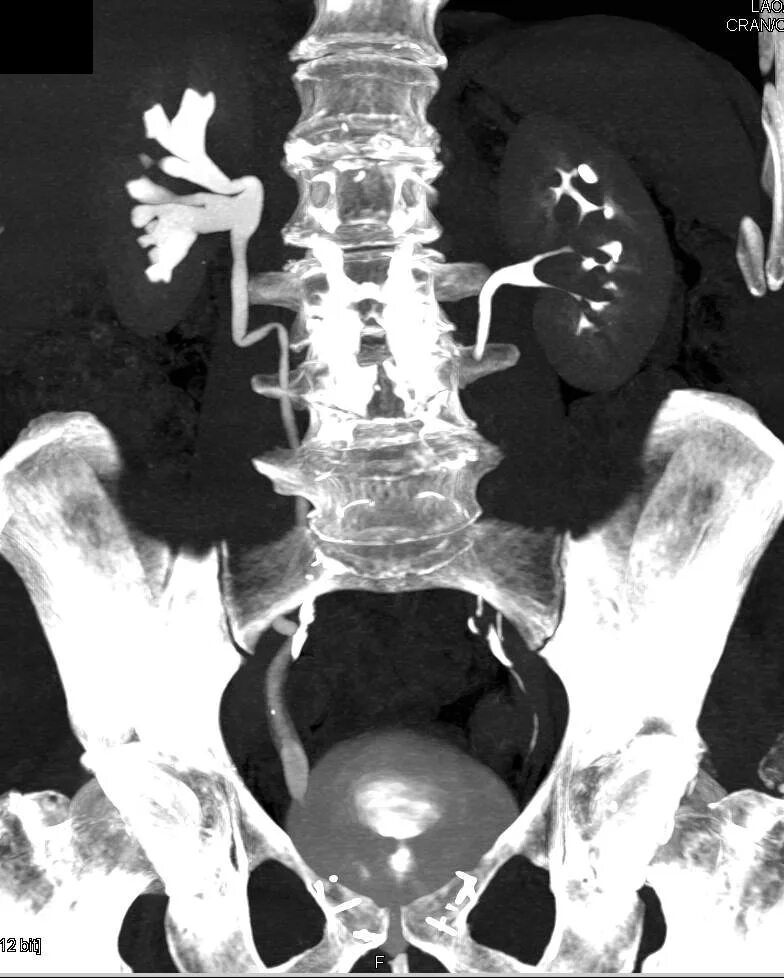

Урография с контрастом